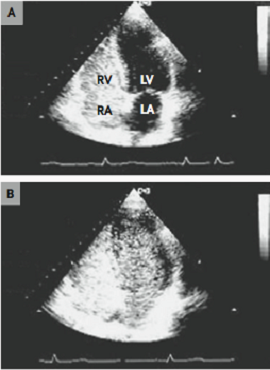

ETT con contraste

(cortocircuito)